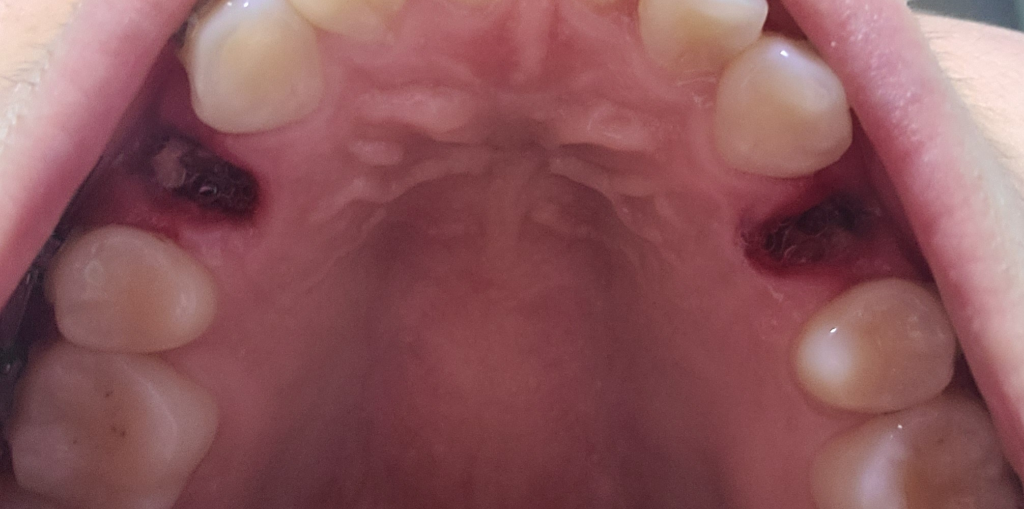

사진상으로는 드라이소켓이나 음식물이 낀 양상은 아니고 잇몸 치유 과정에 나오는 육아조직으로 보여집니다

거즈 잘 물고 있다가 피가 멎었을 때 거즈를 뺐고, 기타 주의사항도 잘 지키셨다면 드라이소켓이나 기타 감염의 가능성은 크지 않습니다